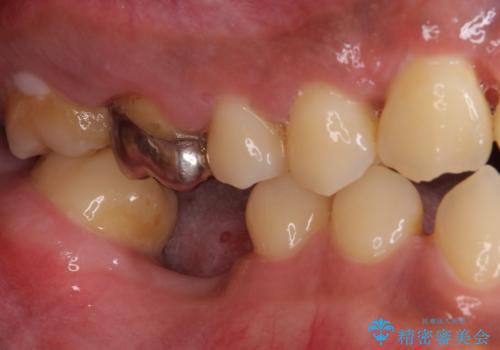

奥歯には元々欠損があり、欠損に伴う咬合不正も認められたため、部分矯正を行った上でインプラント補綴治療も行うこととしました。